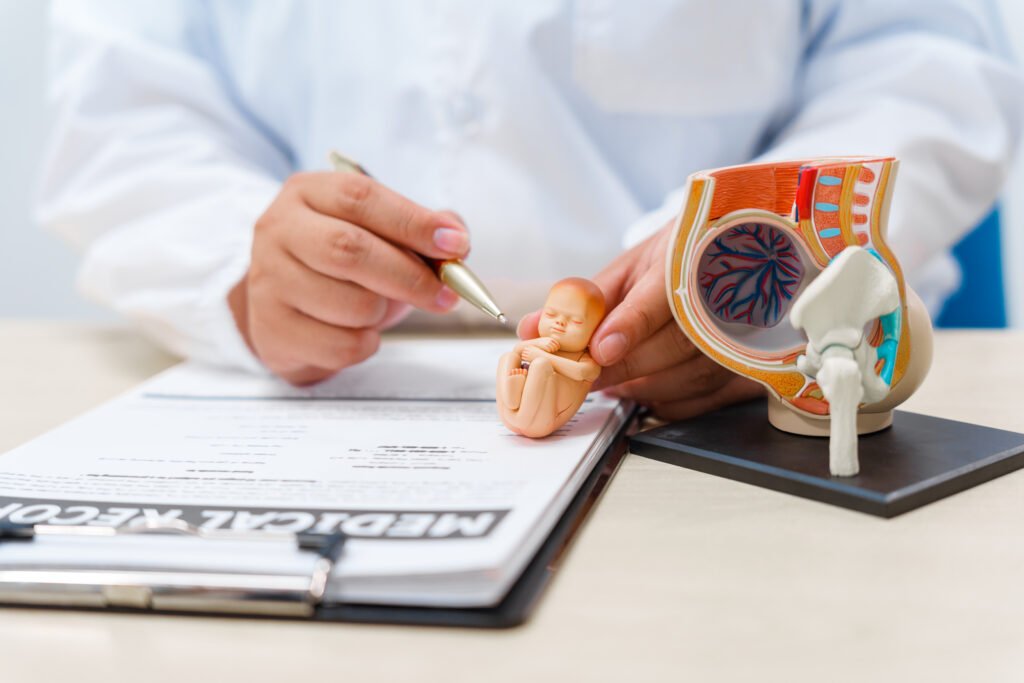

W naszym gabinecie zapewniamy nowoczesne i bezpieczne badania, które wspierają przyszłe mamy od planowania ciąży aż po poród. Oferujemy diagnostykę prenatalną, USG, KTG i testy genetyczne o wysokiej skuteczności. Dzięki indywidualnemu podejściu każda pacjentka otrzymuje nie tylko rzetelną diagnozę, ale również pełne wsparcie i poczucie bezpieczeństwa.

Badania prenatalne pozwalają ocenić rozwój płodu i w porę wykryć nieprawidłowości. Pierwsze badanie wykonuje się w 12–14 tygodniu ciąży, kolejne w 18–22 oraz około 30 tygodnia. Obejmują one USG oraz badania biochemiczne z krwi matki. Współpracujemy z pacjentkami także przy testach genetycznych, takich jak NIFTY czy IONA, które z wysoką skutecznością określają ryzyko wystąpienia wad genetycznych. Badania są w pełni bezpieczne dla mamy i dziecka.